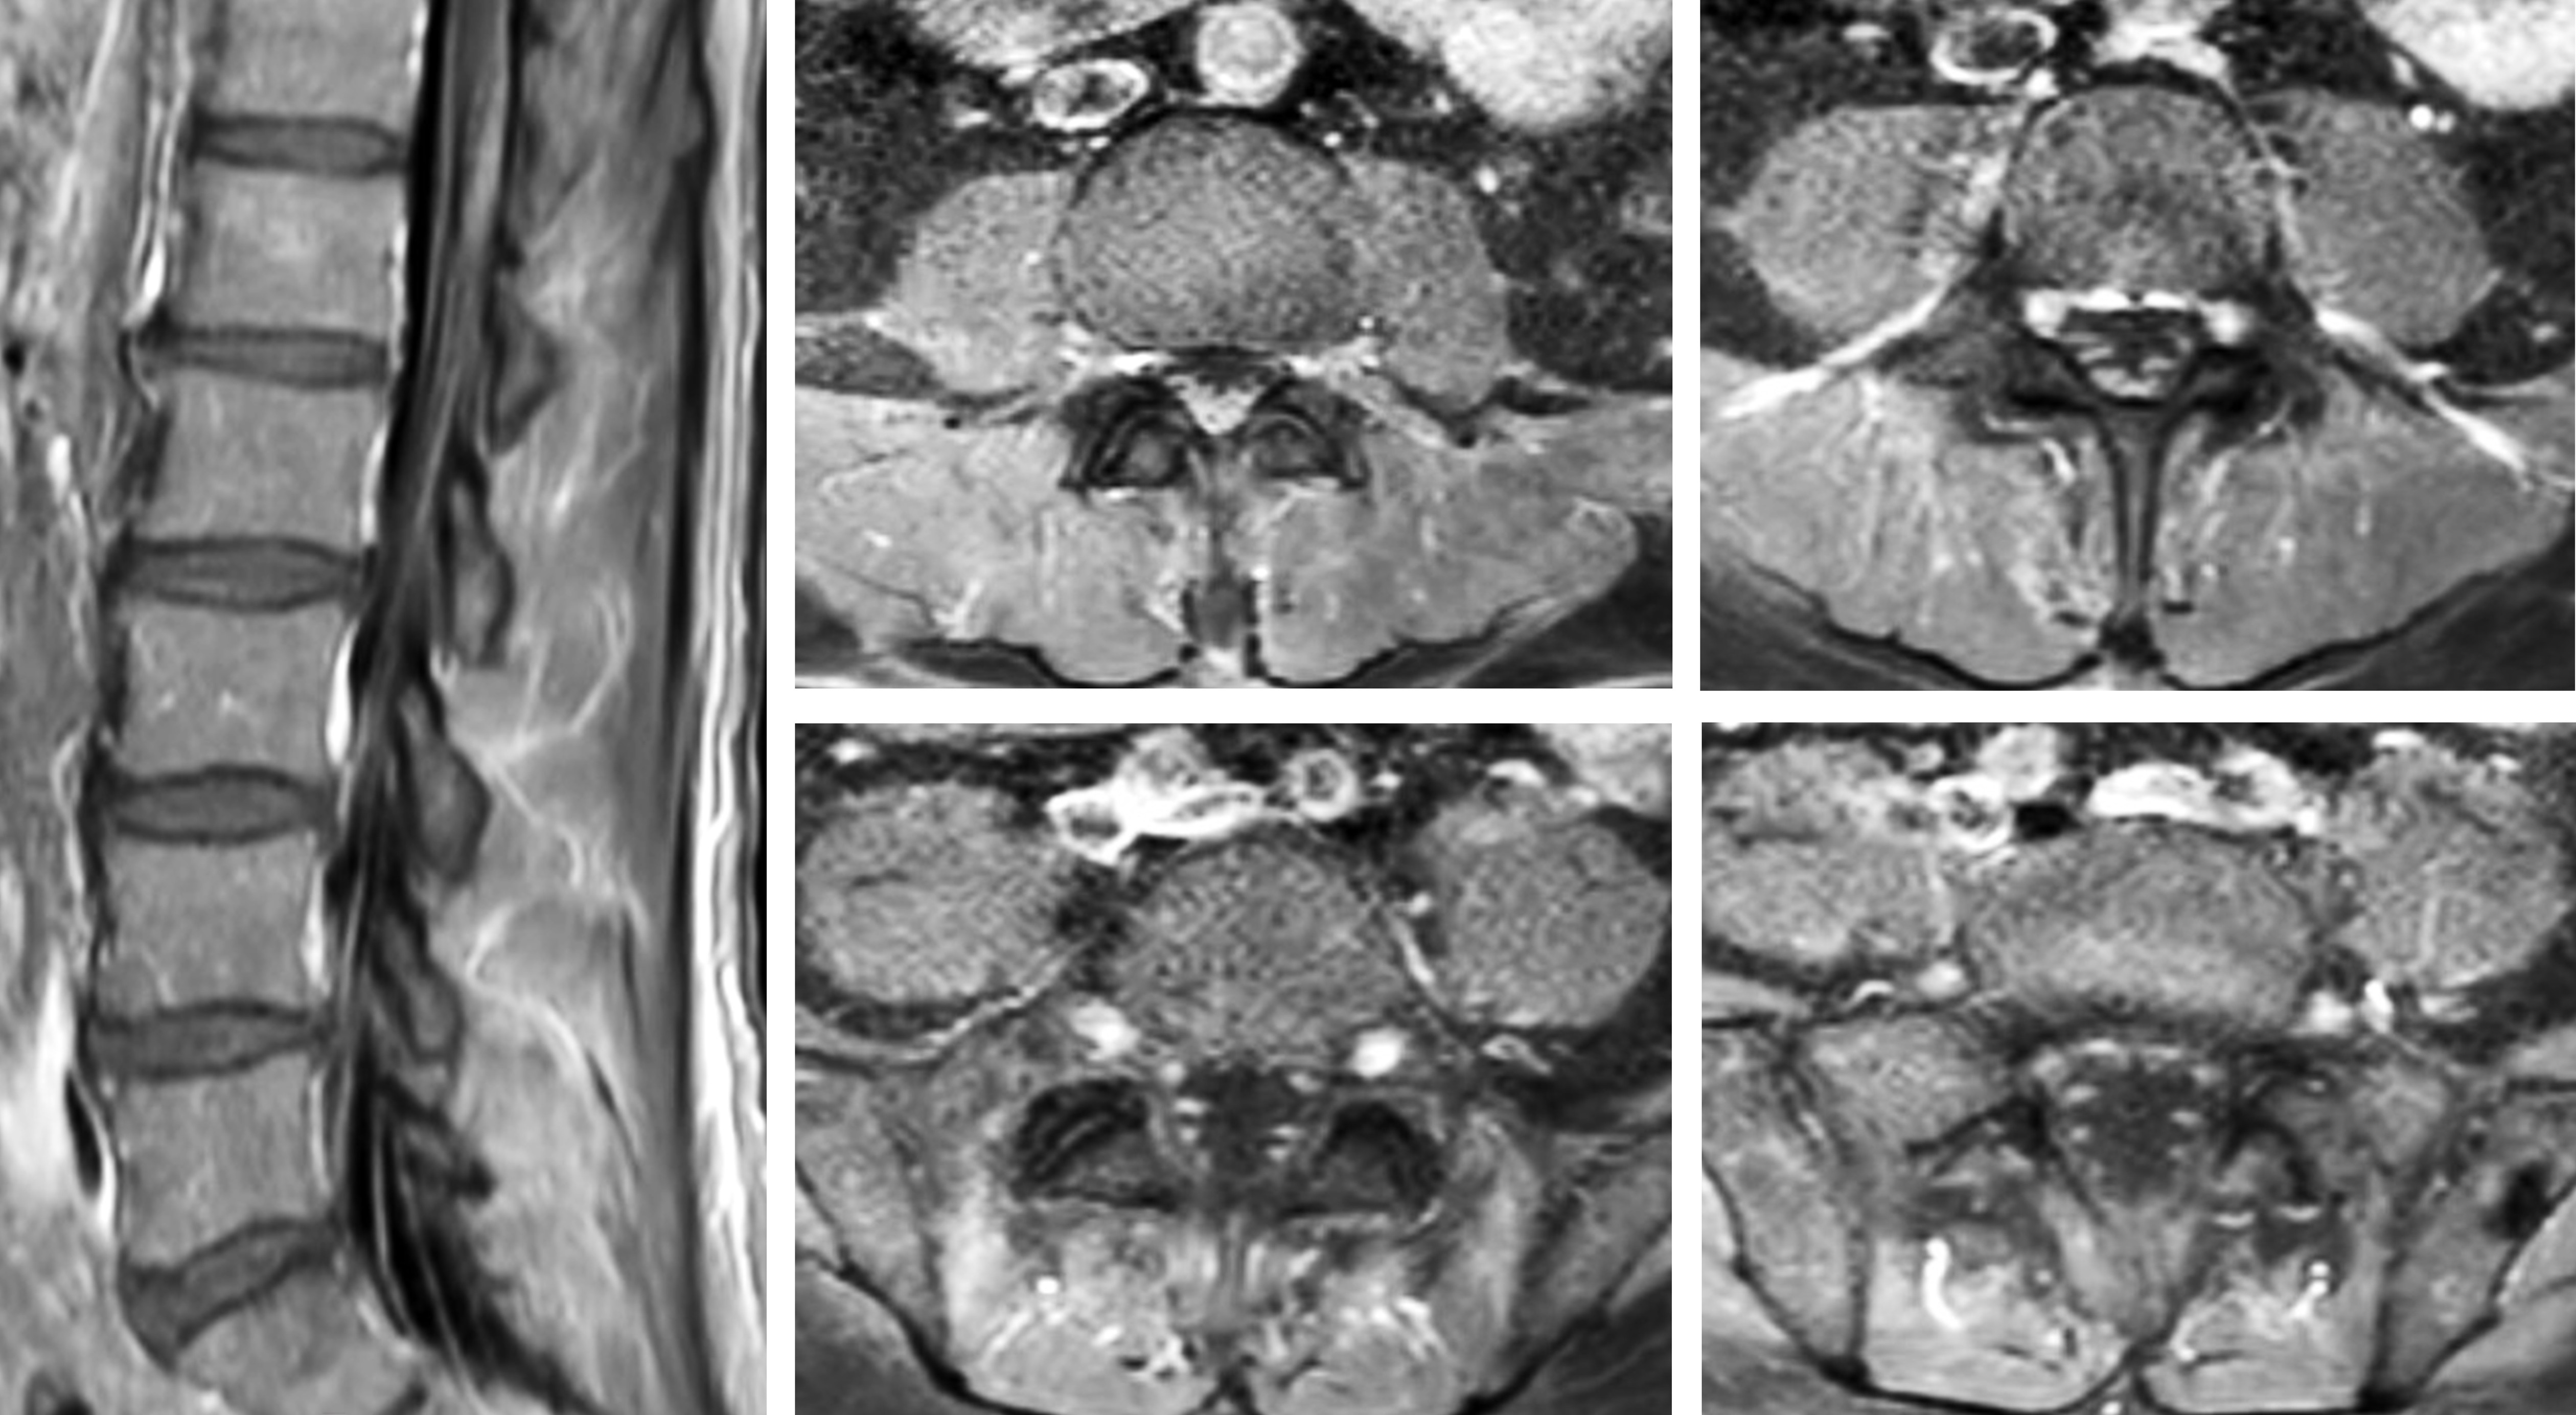

Cases of the Week

Check out our Cases of the Week!